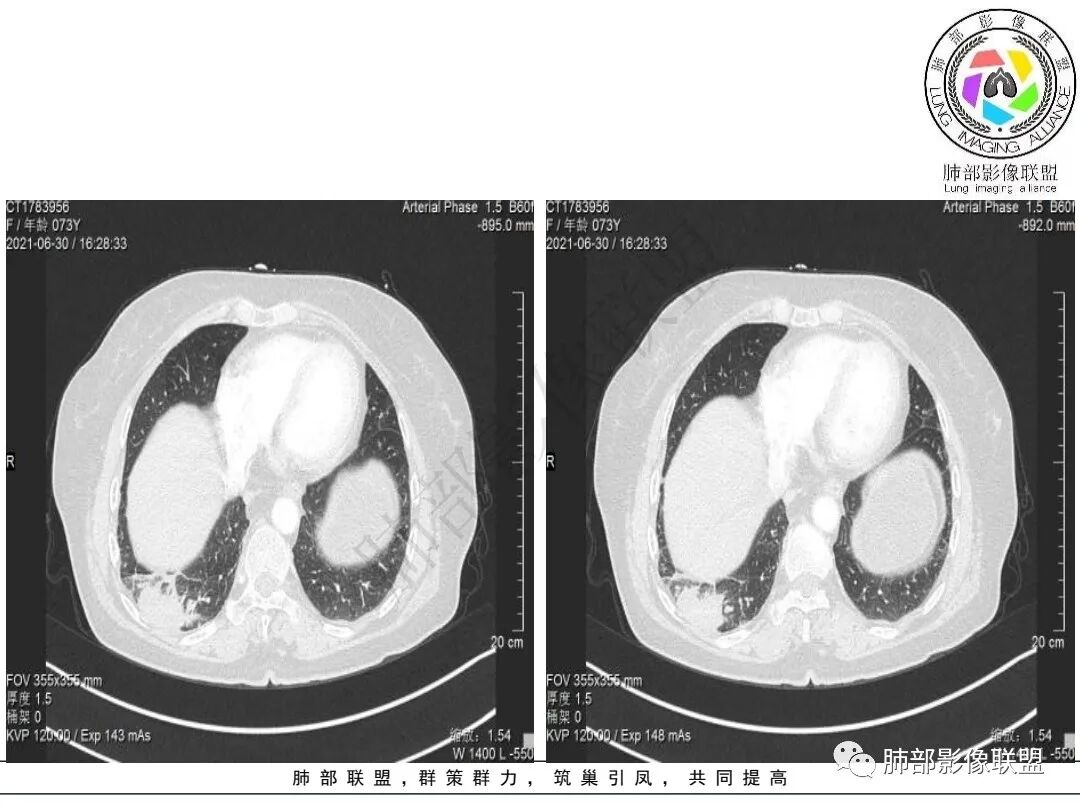

2.右肺下叶不规则实性密度块影,占据外后基底段及背段较大范围,可见轻度分叶、毛刺及棘状突起,未见明显胸膜牵拉及凹陷。

3.右肺下叶支气管轻度狭窄,病灶内见部分充气支气管征,外后基底段不能连续跟踪。

轻度不均匀强化,病灶内小血管显示不满意,未见明确坏死区。

4.右肺门及纵隔见多处增大淋巴结,不均匀环形强化,后下纵隔(隆突下)肿大淋巴结十分显眼!

1)女性不吸烟患者,病灶虽强化不显著,但未见大范围坏死或空洞,肺鳞癌的可能性较小。

2)块影收缩乏力,强化不显著,不是典型的肺腺癌影像学表现。

3)病灶强化不显著,支气管相关,纵隔淋巴结肿大明显,小细胞癌的可能性是比较大的。黄勇老师曾统计后下纵隔(隆突下)显著肿大淋巴结,小细胞癌占比相当高,临床实践也是如此。